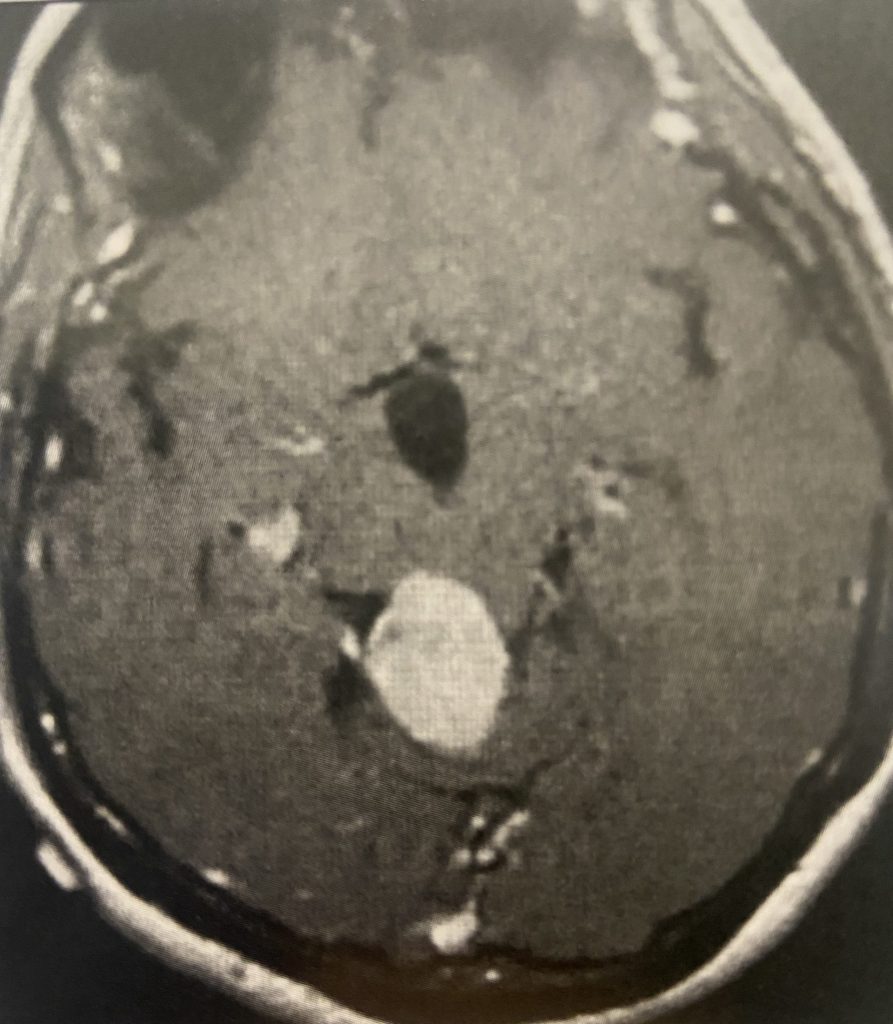

Figure 3

Postoperative post contrast axial MRIs demonstrating complete removal of the tumor with resolution of the hydrocephalus.

Subsequently, the hydrocephalus resolved and the patient did not require shunting. Her pre-operative symptoms all resolved. Follow up MRI demonstrated complete removal of the tumor.